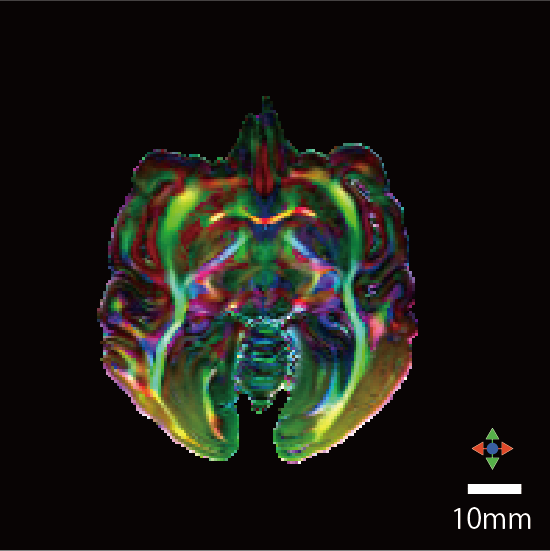

撮像情報

| T2強調画像 | 拡散テンソル画像 | |

| エコー時間 (TE) (秒) | 7.5 | 20 |

| 繰り返し時間 (RT) (秒) | 600 | 650 |

| 励起回数 (NEX) | 3 | 1 |

| 有効視野 (FOV) (mm) | 84, 67.2, 50.4 | 84, 67.2, 50.4 |

| マトリクスサイズ | 320, 256, 192 | 160, 128, 96 |

| 空間分解能 (µm) | 0.21 | 0.53 |

| b0 | - | 2 |

| 撮像時間 | 6時間 43分 | 53時間 14分 |

脳標本画像

| カラーマップ |

![]() |